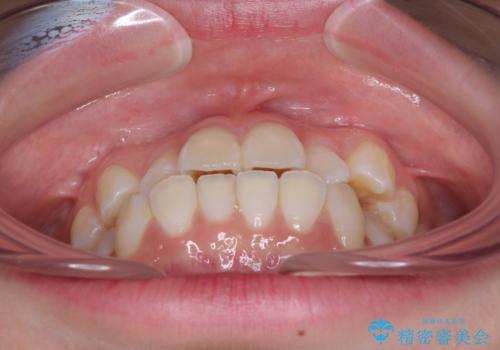

- 海外留学の予定があるが、学生のうちに歯列を整えたいとのことで来院された患者様です。

前歯にデコボコがあり、口元がやや突出した印象があったため、IPR(歯と歯の間を削る)と親知らずを抜歯した上での歯列全体の後方移動をメインに、インビザラインを用いて矯正治療を行うこととしました。

年に一度、夏休みの時期にしか帰国できないため、帰国のタイミングに合わせてマウスピース交換スケジュール治療計画としたため、3年半という期間を要しました。

留学先でもしっかりとマウスピースの装着を実践してくださったので、ご本人の満足のいく仕上がりとなりました。